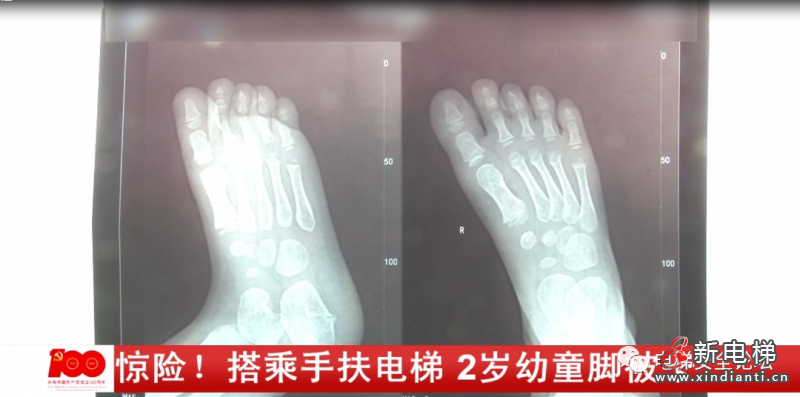

奶奶介紹,當(dāng)時(shí)情況十分危急,孩子的右腳被卡進(jìn)電梯的縫隙里,孩子不停的在哭喊,工作人員將孩子的腳解救出來(lái)時(shí),腳已經(jīng)被卡得變形。小西的奶奶:那只腳小腳趾還好一點(diǎn),其他的腳趾尤其是大腳趾都被卡得白白的扁扁的,我以為我小孩的腳殘廢了,沒(méi)用了。事后,小西被緊急送往附近的醫(yī)院進(jìn)行治療,幸運(yùn)的是孩子受傷的腳并沒(méi)有骨折。